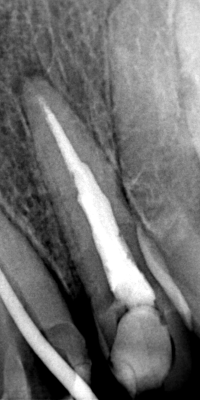

Η ασθενής ταλαιπωρούταν με το συγκεκριμένο δόντι τον τελευταίο ενάμιση χρόνο καθώς το δόντι της είχε απονευρωθεί, αλλά παρόλα αυτά συνέχιζε να την πονάει έντονα. Επρόκειτο για τον πρώτο δεξιό προγόμφιο της άνω γνάθου. Απαραίτητο για τη θεραπεία του δοντιού ήταν η διάνοιξή του και η επανάληψη απονεύρωσης, ώστε να διαγνωσθεί η αιτία πρόκλησης πόνου. Πράγματι μετά την αφαίρεση της παλιάς έμφραξης διαπιστώθηκε οτι το δόντι είχε διατρηθεί από παλαιότερες οδοντιατρικές εργασίες, ενώ η δεύτερη ρίζα του δοντιού δεν είχε βρεθεί, καθαρισθεί και εμφραχθεί ποτέ. Μετά την έμφραξη της διάτρησης του δοντιού ακολούθησε η επανάληψη της απονεύρωσης. Πιο συγκεκριμένα από τη μία ρίζα του δοντιού αφαιρέθηκε η παλιά απονεύρωση, ενώ η δεύτερη ρίζα εντοπίστηκε, επεξεργάστηκε και εμφράχθηκε για πρώτη φορά (κάτι βέβαια που θα έπρεπε να είχε γίνει από την προηγούμενες οδοντιατρικές θεραπείες). Η τελική ακτινογραφία παρουσιάζει το άκρως ικανοποιητικό αποτέλεσμα της επανάληψης απονεύρωσης. Η θεραπεία ολοκληρώθηκε σε 2 μόλις συνεδρίες και η ασθενής είναι πλήρως ικανοποιημένη με τη λειτουργία του δοντιού.

ΠΡΙΝ

ΜΕΤΑ